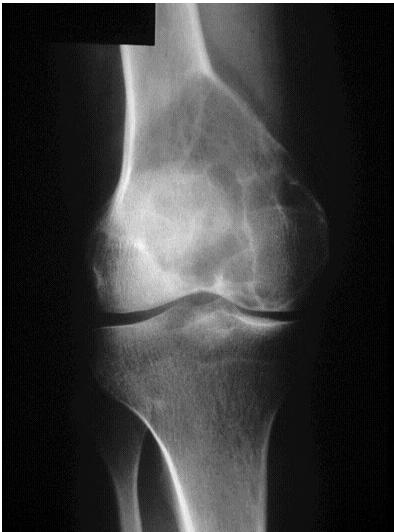

Giant Cell Tumor

site: distal femur size: Most (involving how much? / cm?) matrix: mixed - mainly radiopaque , wide zone of transition, cortical destruction, resulted periosteal reaction, and codman’s triangle soft tissue involvement: